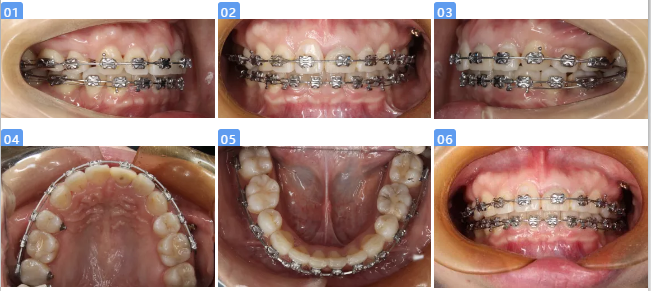

五、治疗结束

1.微笑美学改善,患者治疗前前牙残根、龋坏、牙龈炎,严重影响微笑美观。通过系统化治疗,恢复前牙的形态、获得牙龈健康、牙齿良好的排列。使得笑容美观得到提升。

2.21牵引修复,21残根长度12mm,牙槽骨内根长11mm,完善根管治疗术后,通过矫正合向牵引2mm,骨内剩余长度9mm,最终完成桩冠修复,冠根比例1:1。21在使用过程中健康稳定。

3.侧貌美观,正畸治疗在关闭多颗(14、24、35、45、17)拔牙间隙过程中,为避免过度内收影响患者面型美观,采取下颌弱支抗、上颌中等支抗设计,最终内收完成上下前牙处于理想位置,收获良好的侧貌美观。

4.后期稳定性。患者患龋风险高,通过问诊检查发现与饮食习惯以及口腔保健意识有直接关系,治疗过程中通过OHI,患者掌握较好的刷牙、牙线使用方法,同时戒除碳酸饮料,1年复查没有新发龋坏,并且通过菌斑染色显示菌斑控制良好。